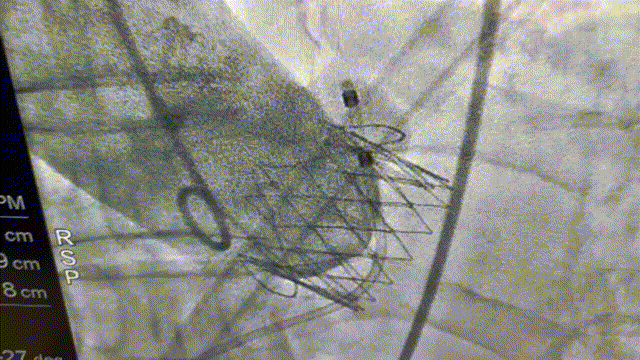

病例一植入后造影